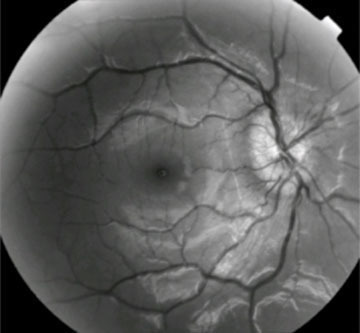

Œdème papillaire de stase au cours d'une hypertension intracrânienne compliquant un thrombophlébite cérébrale dans le cadre d'une maladie de Behçet.